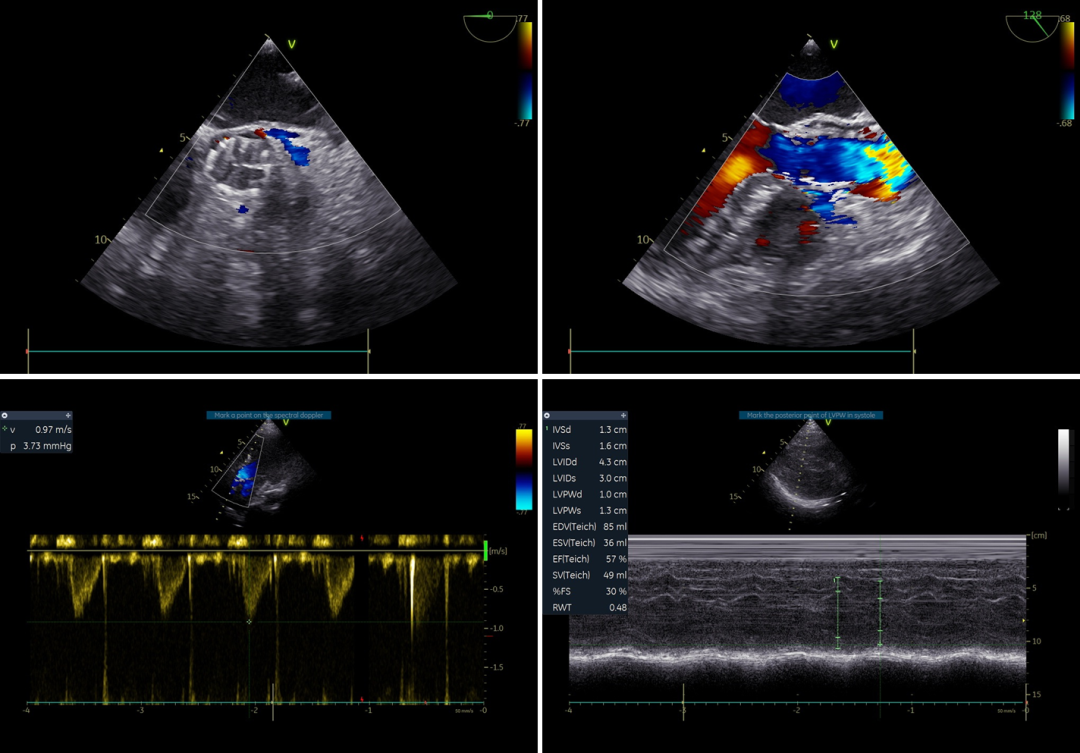

76岁女性患者,主因“间断心悸、头晕5年,加重1个月”入院,既往高血压、房颤病史,NYHA IV级。术前超声提示主动脉瓣重度关闭不全,LAD 39mm,LVEDD 59mm,LVESD 39mm,LVEF 59%,LVEDV 165ml,LVESV 67ml,LW/LVOH 47%,VC 0.33cm。

术后血流动力学

瓣膜展开良好,无明显瓣周漏;人工瓣膜流速0.97m/s,压差3.73mmHg;植入后30min,EDV 85ml(术前165ml),ESV 36ml(术前67ml)